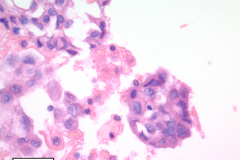

Cytology: Cytologic features suggestive of epithelioid hemangioendothelioma include spindle or polygonal epithelioid cells with moderate to abundant dense cytoplasm, well-defined cytoplasmic borders, and intracytoplasmic vacuoles and may present as single cells, small clusters or sheets. The large, eccentric nuclei are mildly pleomorphic with nuclear grooves, and nuclear cytoplasmic inclusions along with finely granular chromatin, irregular nuclear membranes, and nucleoli.4,5 Histologic features commonly seen in EHE include myxoid stroma, hyalinized stroma, and chondromyxoid stroma, as well as infrequent-to-frequent mitoses, erythrocytes, and a general absence of necrosis.3,4

Nuclear grooves and erythrocytes can be seen in the cell block (Image 3).